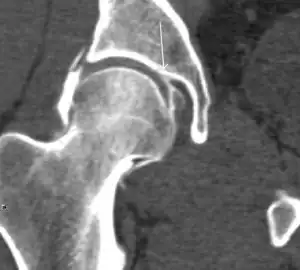

Slipped capital femoral epiphyses (SCFE) usually affect 11- to 14-year-old adolescents (Figure 4). Radiographs may show widening and irregularity of the physis and posterior inferior displacement of the capital femoral epiphysis. On the AP view Klein’s line, tangent to the lateral aspect of the femoral neck, does not intersect the femoral head indicating that it is displaced. SCFE may compromise the blood supply to the femoral head and cause avascular necrosis, mainly when there is instability between the fragments.[1]

-

Figure 4: (a) X-ray of a 10-year-old child with left hip pain. It was considered normal at emergency despite the widening of the left physis (arrow). Two weeks later epiphysiolysis was evident (b). Despite appropriate surgical reduction (c) osteonecrosis developed and femoral head collapsed 1 month later (d).[1]